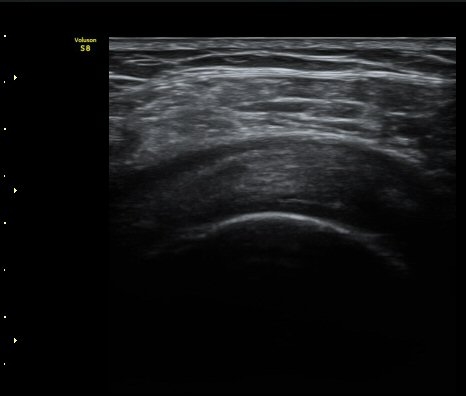

ÃÊÀ½ÆÄ °Ë»ç

¾î±ú À̵ιڱ٠Ⱦ´Ü¸é°Ë»ç¿¡¼­ ½ÉÇÑ Á¡¾×³¶³» ¼ö¾×Àú·ù°¡ °üÂûµÇÁö¸¸ ÆÄ¿öµµÇ÷¯

°Ë»ç¿¡¼­ Ç÷·ùÁõ°¡´Â °üÂûµÇÁö ¾Ê´Â´Ù(±×¸² 1, 2).   À̵ιڱ٠¾Æ·¡ Ⱦ´Ü¸é°Ë»ç¿¡¼­